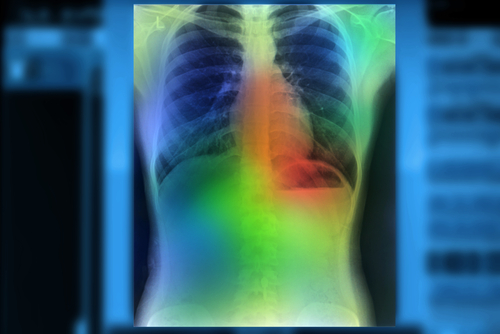

The technology has been trained on more than one million chest x-rays so far. Taking only milliseconds to run, the product uses a heat map or bounding box to point out abnormalities to the clinician, facilitating rapid confirmation. In settings without trained healthcare professionals, qXR is already being used to screen for tuberculosis, proving a valuable supplement to the existing healthcare systems. There are fewer than five companies globally who have received a CE certification for AI-based radiology products.

"The chest x-ray is the most commonly-performed radiology investigation, but one of the toughest to interpret," said Dr. Shalini Govil, Quality Controller for the Columbia Asia Radiology Group. "Qure.ai's solution could serve as a radiology assistant, providing a draft report that can be validated by a physician or radiologist. They've also come up with technology to visualize what the algorithm sees - a way to 'see through the computer's eyes'. I think this will be a game-changer on the road to building confidence in AI."